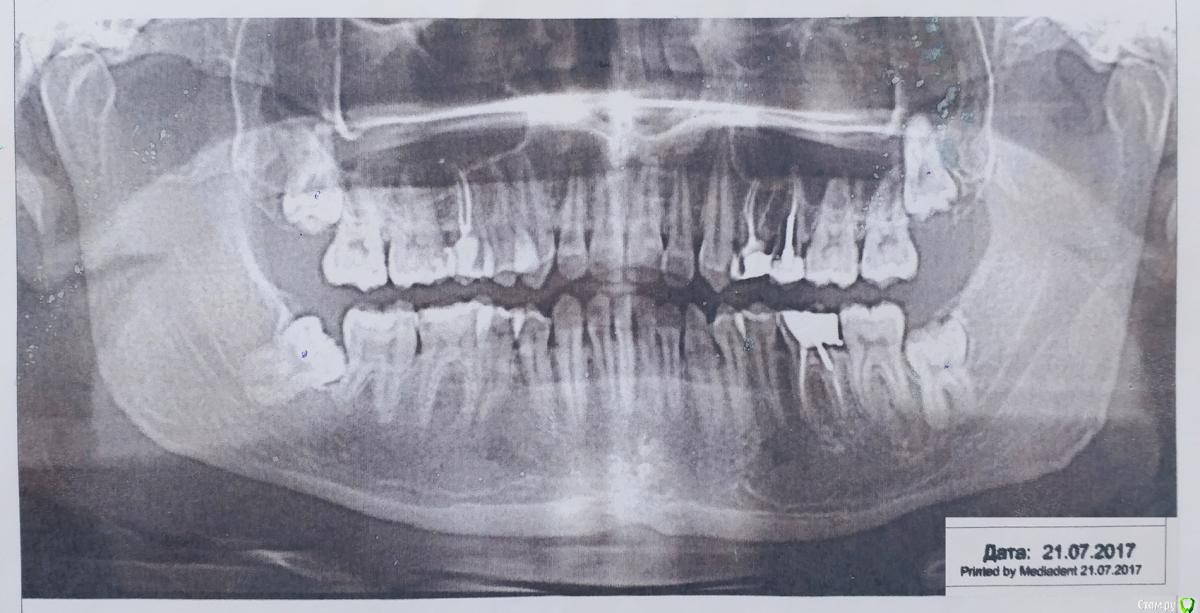

На снимках обнаружились дистопированные-ретинированные зубы мудрости.

post-54820-0-96917100-1523282064_thumb.jpg

В сентябре, с перерывом в 3 недели удалил оба нижних. Операции шли по 20-30 минут (с учетом анестезии), хирург спокойный и аккуратный. Во время второго удаления всё же пришлось оказывать давление на челюсть в процессе, так как зуб засел очень глубоко и была плотная кость.